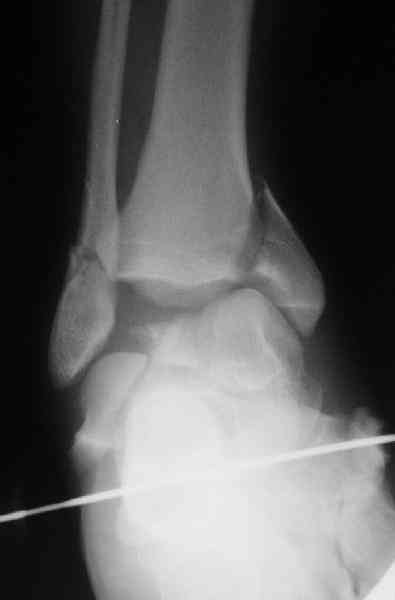

Случай с множественным оскольчатым переломом тарана оперированный из двойного доступа.

Через 2 мес.:

Через 8 мес.:

Через 14 мес.: